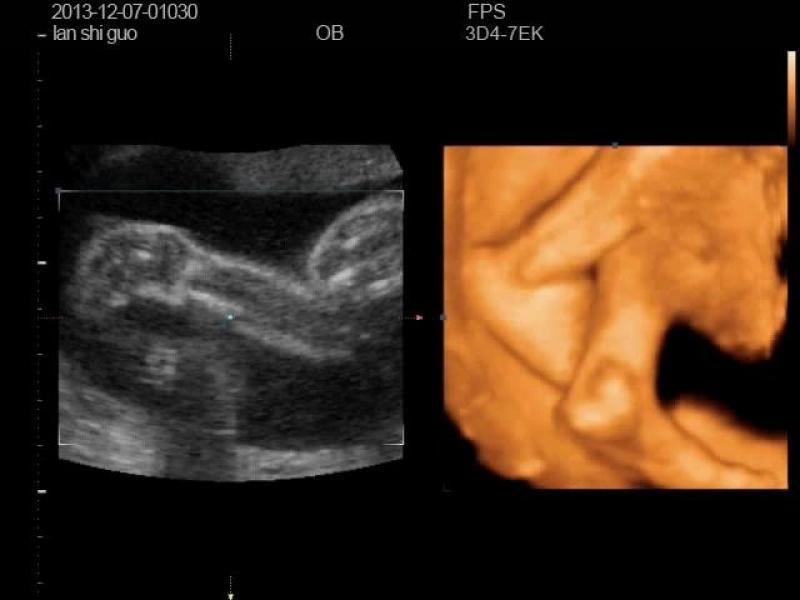

我前两天照的四维彩超,看着宝宝脚好别扭啊,哪位专家帮我看看,是不是有问题

四维彩超就是影像学,看宝宝的称笼尺外形和器官有没有明显缺陷的,如果有问题,医生肯定会告诉你的。拍摄角度也会影响效果,如果医生说一切药扬安好,宝妈就不要太担心啦。长饱满了就好裕佳啦